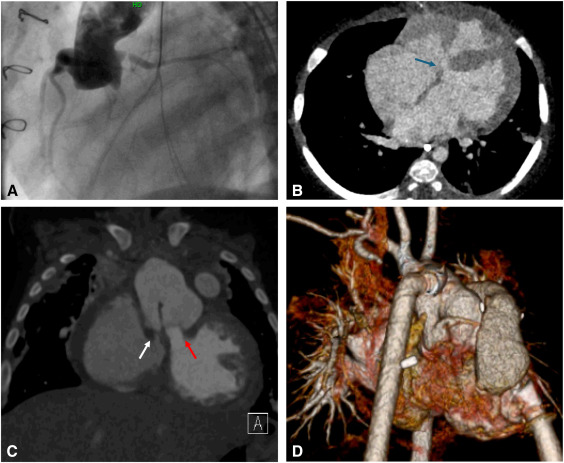

.⁦Kendall Lawrence⁩ , Nimesh Desai MD PhD, Michael Catalano, MD, and Cecillia Chin (Lui) describe the approach to a complex aortic arch and descending thoracic aortic reconstruction following infection of a thoracic branched endograft. academic.oup.com/icvts/article/…

The bare metal AMDS stent yields key benefits in the management of patients with DeBakey I aortic dissections, promoting positive remodeling with a familiar hemiarch operation. What role should it play in dissection management? We discuss in our review: authors.elsevier.com/a/1lWBZ3jAej9N…

The bare metal AMDS stent yields key benefits in the management of patients with DeBakey I aortic dissections, promoting positive remodeling with a familiar hemiarch operation. What role should it play in dissection management? We discuss in our review:

authors.elsevier.com/a/1lWBZ3jAej9N…

PennSurgery (@pennsurgery) 's Twitter Profile Photo

In an expert review piece, Michael Catalano, MD, Chase Brown, MD, MS, and Dr. Szeto describe the indications, surgical approach, and key considerations of the novel bare metal AMDS stent for type A dissection management. researchgate.net/publication/39…